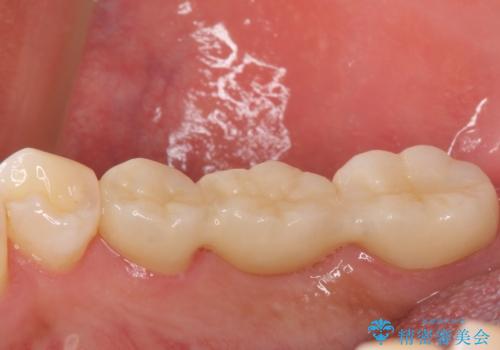

精度の高いブリッジなので、しみるなどの症状もなく経過も良好です。